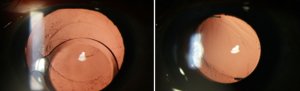

Preoperative Post op 4 months

(IOL exchange with SFIOL )

Fig 1.(a)Preoperative- Complete IOL dislocated (b) IOL exchange with Scleral fixated IOL